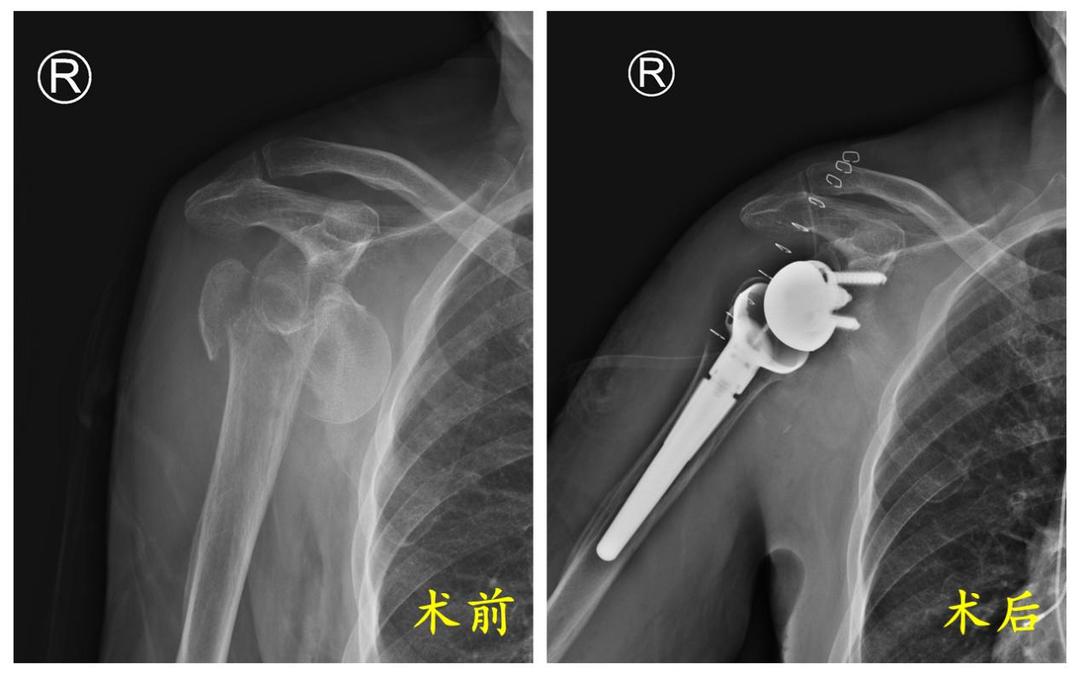

到达医院后,李女士被迅速推进急诊创伤外科病区。医生们立即为她安排了一系列检查,X光片和CT扫描结果显示,李女士右侧肱骨近端粉碎性骨折,属于Neer分型四部分骨折。这种骨折在老年骨质疏松患者中较为常见,但情况却相当棘手——骨折块移位明显,血运破坏严重。

团队深入分析李女士的骨折特点,骨折块粉碎严重,移位明显,这使得传统的钢板螺钉内固定治疗困难重重。不仅复位固定难度大,手术时间长,术中出血多,而且术后还面临骨折不愈合、肱骨头坏死塌陷的极高风险。术后漫长的康复期,对于高龄的李女士来说,也是一个严峻的考验。

在充分讨论李女士的康复需求后,急诊创伤外科病区团队一致认为,帮助李女士尽快恢复肩关节功能,减少卧床时间,降低并发症风险,提高生活质量,才是治疗的关键。经过审慎权衡与充分论证,大家认为,相较于传统内固定方案,“反向肩关节置换术”才是更适合李女士的最佳选择。

“反向肩关节置换术”是肩关节外科领域一项技术含量高、操作复杂的前沿技术,属于国家规定的最高难度级别——四级手术。其设计理念独特,通过将人工肩关节的球与臼位置对调,改变了肩关节的生物力学传导,使得功能恢复不再依赖于严重受损且难以愈合的自身肩袖组织。这对于伴有严重骨折和肩袖功能不良的老年患者而言,能更有效地重建肩关节功能,显著减轻疼痛,并允许术后早期进行功能锻炼。